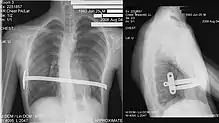

الدكتور دونالد نوس، في مستشفى كنجز دوتر للاطفال في نورفولك، فيرجينيا، قام بأول عملية جراحية لمعالجه الصدر المقعر في عام 1987[29] وصرح بهذه العملية في مؤتمر عام 1997.[30][31] وتم تسميتها بعمليه نوس، وهي تتم عن طريق زراعة قمع صلب كهفي الشكل اسفل عظمه القص. وهذا القمع يتم دفع العظم إلى الخارج مما يؤدي إلى تخفيف التشوه. يظل هذا القمع في جسم المريض سنتين تقريبا. وبعض الجراحين يميلون إلى أبقاءها في الجسم إلى خمسة سنوات إلى أن يثبت العظم في محله. ثم يتم إزلته عن طريق عمليه في العيادات الخارجية.

في البداية كانت عمليه نوس تستخدم للأطفال الأقل من عشر سنوات لان عظمه القص والغضاريف أكثر مرونه. كما ان نسبه نجاح العملية في صغار السن أكثر بكثير من كبار السن. تتم عن طريق عمليتين منفصلتين.